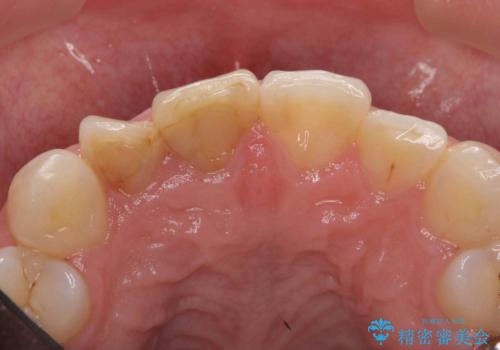

前歯の変色 セラミッククラウンによる審美性の回復

- 前歯が徐々に神経の治療を行ってから変色し、審美性の回復を求めて来院されました。

根尖に病変は見られず、根管治療は行わずに仮歯・ジルコニアクラウンを作製、装着することで審美性を回復しました。